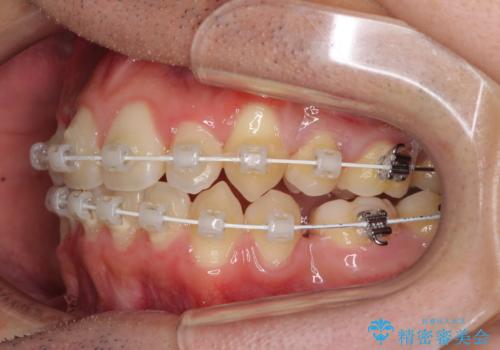

- 矯正装置

- 審美装置

- 治療期間

- 2年10ヶ月

- 上下の八重歯や乱杭歯を気にして来院され患者様です。

スペースを確保するため、上下左右の小臼歯を抜歯し、ワイヤー装置に矯正することとしました。

奥歯の咬み合わせの左右差が大きかったため、変則的な抜歯矯正を行いました。

治療期間はやや長期化しましたが、満足のいく歯並びとなりました。